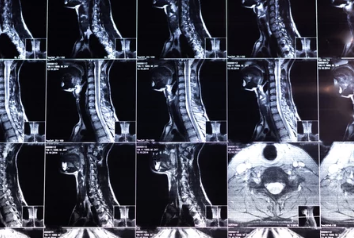

1. 목디스크란 무엇인가?

목디스크의 정의

목디스크(경추 추간판 탈출증)는 목뼈 사이에 있는 디스크(추간판)가 탈출하거나 찢어져 신경을 압박하는 상태를 말합니다. 이로 인해 통증, 저림, 움직임 제한 등이 발생합니다.

6. 수술적 치료 방법

수술이 필요한 경우

- 약물 및 물리치료에도 증상이 호전되지 않는 경우.

- 신경이 심각하게 눌려 근육 약화나 마비가 발생한 경우.

주요 수술법